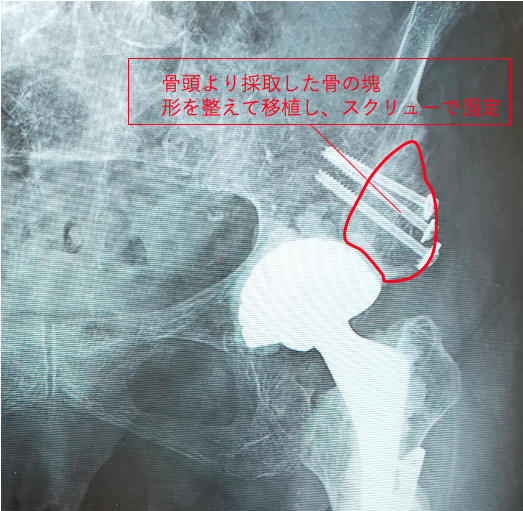

今回の症例では、まず左股関節症に対して大腿骨短縮骨切り併用THAを行いました。

正確な人工関節の設置が非常に難しいため、3Dテンプレートによる綿密な術前計画と、患者様ご本人の実物大の3D骨モデルを作成し、手術を行いました。

3Dテンプレートにより、3次元で評価することができるため、より適切な機種、設置位置などを再現することが可能です。

骨モデルで実際の人工関節の設置角度や骨欠損の状態をより正確に把握することができます。

骨の欠損も著しく、自身の骨より採取した骨を移植(自家骨移植)し、人工関節の土台とします。